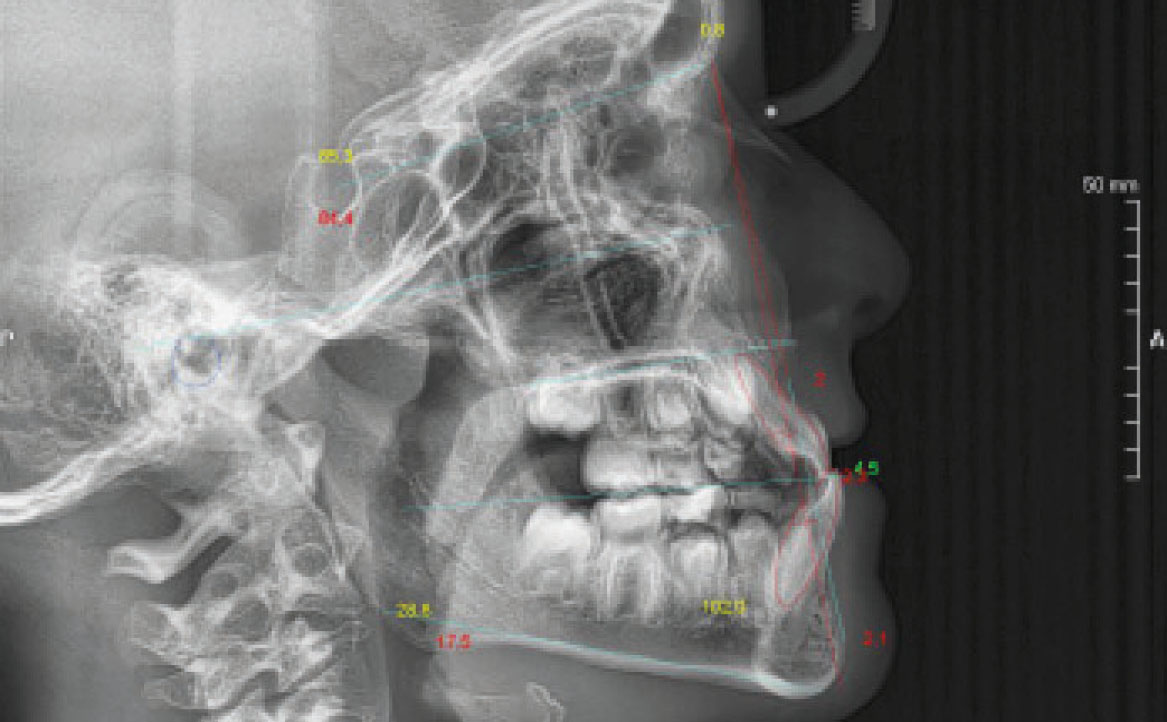

Dal tracciato cefalometrico eseguito su teleradiografia L/L ne risulta I classe scheletrica (tendente alla III classe) ipodivergente con retroinclinazione degli incisivi superiori e proinclinazione degli incisivi inferiori (fig. 2-3).

Fig. 3 Teleradiografia latero-laterale.